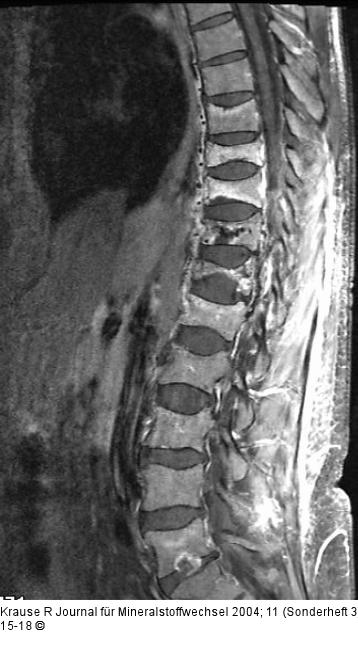

Abbildung 2: Wirbelkörper - Kompression T1-gewichtetes Bild der BWS/LWS in seitlicher Schnittführung, mit Fettunterdrückung und nach Gabe von Gadolineum bei Patientin aus Fall 1 nach Vertebroplastie. Es ist noch die ausgeprägte Kompression der Wirbelkörper BWK11 und 12 zu erkennen. Außerdem Kontrastmittelaufnahme in den Wirbelkörpern BWK9 und 10 als Zeichen der neu aufgetretenen Sinterungsfrakturen. |

T1-gewichtetes Bild der BWS/LWS in seitlicher Schnittführung, mit Fettunterdrückung und nach Gabe von Gadolineum bei Patientin aus Fall 1 nach Vertebroplastie. Es ist noch die ausgeprägte Kompression der Wirbelkörper BWK11 und 12 zu erkennen. Außerdem Kontrastmittelaufnahme in den Wirbelkörpern BWK9 und 10 als Zeichen der neu aufgetretenen Sinterungsfrakturen. |